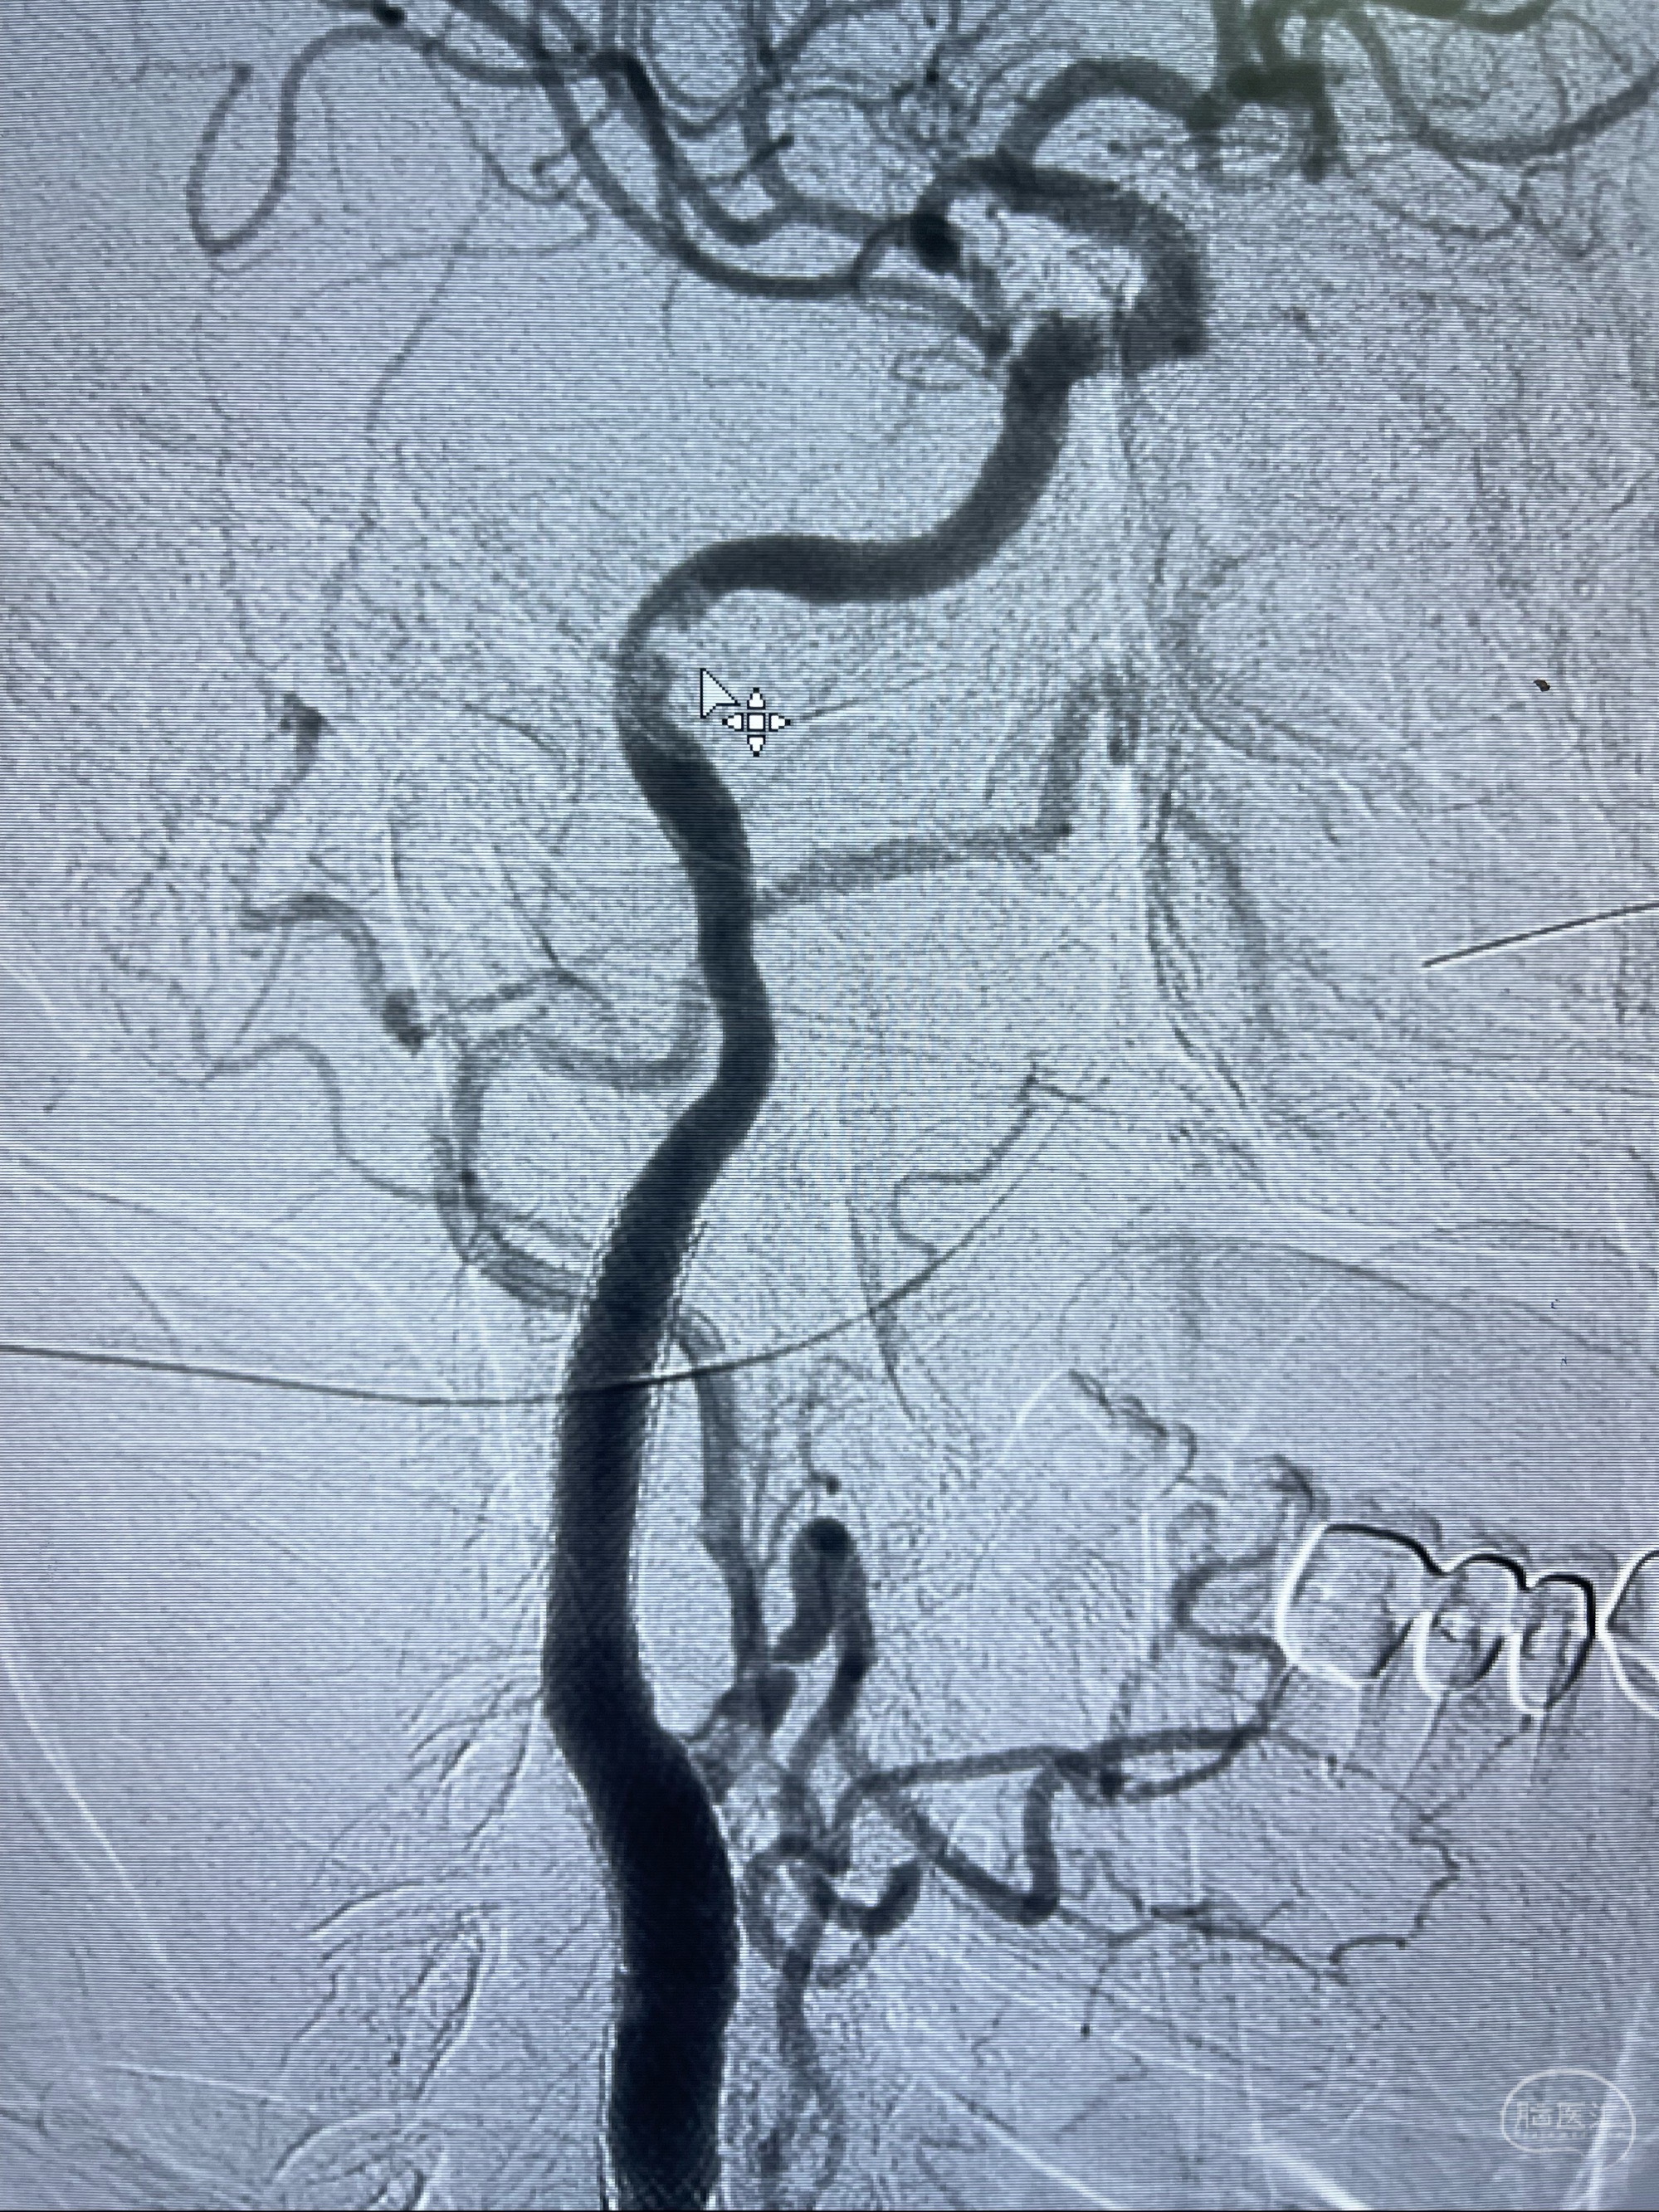

重新行“路径图”,支架导管在微导丝引导下超选择性插入至右侧颈内动脉眼段,4.5-50mmLeo支架释放,远心端位于海绵窦段,近心端位于岩骨段狭窄段以近

即刻造影显示支架贴壁佳

路径图下,5.5-50mmLeo支架导管在微导丝引导下超选择性插入远段Leo支架内

两枚支架部分重叠

多次确认支架位置及打开贴壁情况

支架完全打开,近心端位于原颈动脉支架远心端内